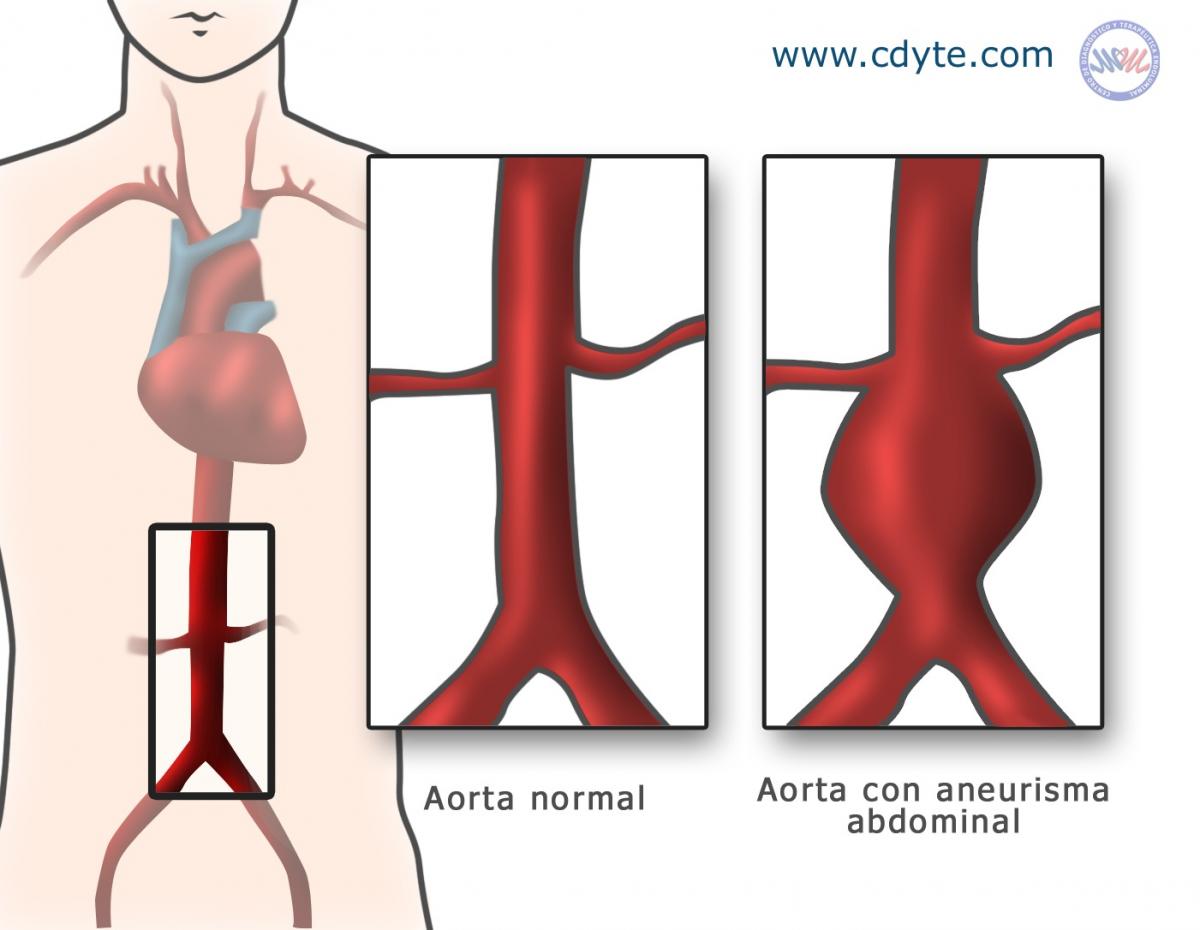

aneurisma de la aorta abdominal La aorta va desde el corazón hasta el. Recibe sangre con gran contenido en oxígeno. Cirugía vascularrupturas de aneurisma de la aorta abdominal: La cirugía de reparación abierta de aneurisma aórtico abdominal (aaa) se realiza para arreglar una parte dilatada de la aorta. Si tienes un aneurisma de la aorta abdominal en expansión, podrías notar lo siguiente: La incidencia de aaai en. En este artículo examen físico pruebas de detección y de diagnóstico ¿quiénes deben someterse a un examen de detección de aneurisma de aorta torácica? Los aneurismas aórticos aneurismas aórticos la aorta, que mide alrededor de 2,5 cm de calibre o diámetro, es la arteria más grande del cuerpo.

Aorta Abdominal / Abdominal Aortic Aneurysm Cardiovascular